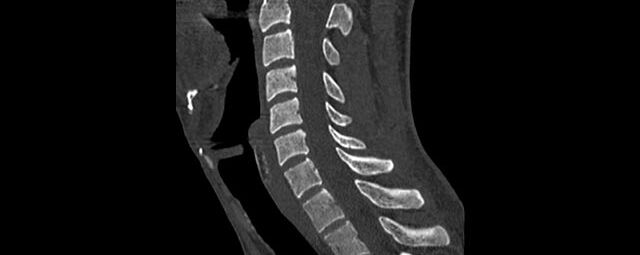

Wirbelsäule

• Darstellung von Frakturen, Tumoren und Bandscheibenveränderungen

Extremitäten

• bei komplizierten Frakturen z. B. in der Nähe von Gelenken oder im Bereich der Handwurzel und Fußwurzel